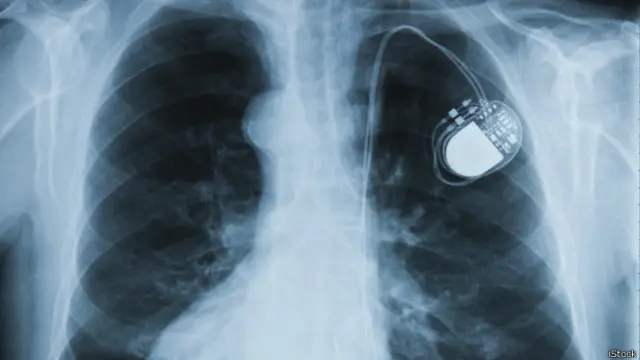

"Мы зависим от закупок оборудования из-за рубежа. Все предметы, которые вставляются в сердце, - кардиостимуляторы, окклюдеры и другие прекрасные "заплатки" [для сердца] - это все куплено на валюту", - сообщила в среду в <link type="page"><caption> интервью программе "БибиСева"</caption><url href="http://www.bbc.co.uk/russian/multimedia/2014/12/141217_bbseva_rouble_fall_charity.shtml" platform="highweb"/></link> директор фонда Екатерина Бермант.

"Российские аналоги есть, но в детской кардиохирургии они просто не подходят, - рассказывает, в свою очередь, Ольга Голенко из фонда "Детские сердца". - Например, те стимуляторы, которые входят в квоту, иногда элементарно не подходят по физиологии. Их трудно подшить".

Автор фото, iStock